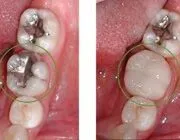

Old amalgam filling on 1st molar was replaced with ceramic crown (Cerec). It took only 1 hour. The Cerec crown is strong, more esthetic, and it is 100% natural material.